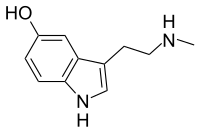

| Nω-Methylserotonin (norbufotenin) | Plants | 5-OH | H | CH3 | 5-hydroxy-N-methyltryptamine | 1134-01-6 |